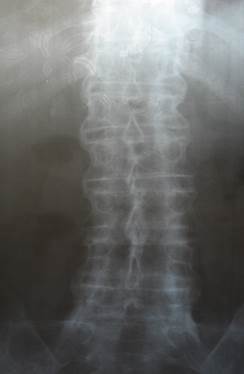

Кеуде Р-граммасы   Жамбас сү йектері рентгенограммасы екіжақ ты сакроилеит белгісінің болуы   Омыртқ аның бел-сегізкө з бө лігінің 2-жақ ты проекциясындағ ы рентгенограммасы 1, 0 0, 5